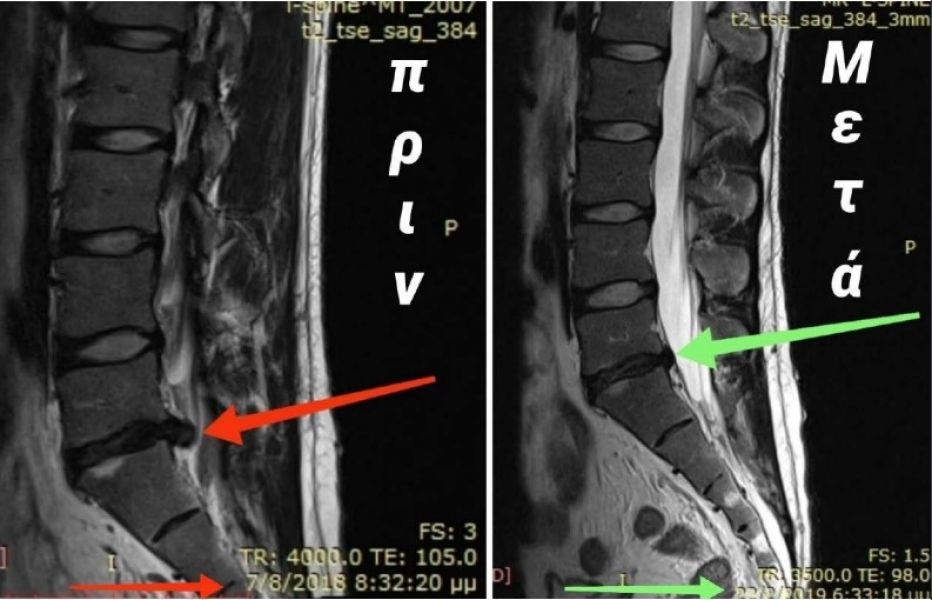

Συρρίκνωση οσφυικής δισκοκήλης μέσης σε ανδρα 46 ετών